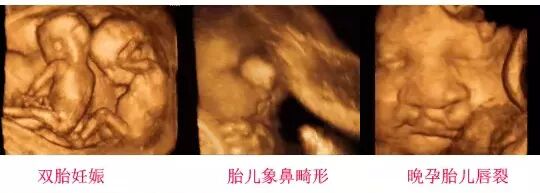

四维彩超的全称为四维彩色超声诊断仪,是目前世界上最先进的彩色超声设备。其领先的科技性,检查时能够表面成像,能够显示出胎儿的实时动态活动图像,或者其它人体内脏器官的实时活动图像。由于四维彩超能够表面成像,胎儿的唇腭裂、四肢发育畸形、脑膜膨出、脊柱裂、腹壁裂等先天畸形能更清晰地查出来。四维彩超的诊断资料有利于医生检测出各种异常,对于胎儿的成长发育做出准确的判断。

四维彩超胎儿畸形筛查

胎儿面部畸形:如唇腭裂等。

神经系统:无脑儿、脑积水、小头畸形、脊柱裂及脑脊膜膨出。

其它畸形:短肢畸形,联体畸形,唇裂、四心腔。